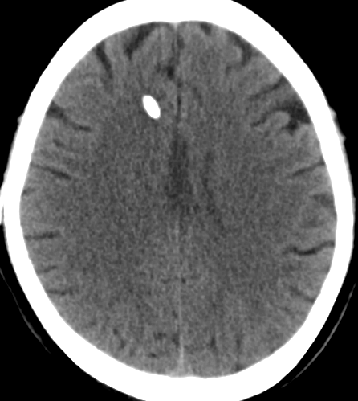

2013-8-12 CT

2013-8-13 调压130——150,头痛症状无明显好转